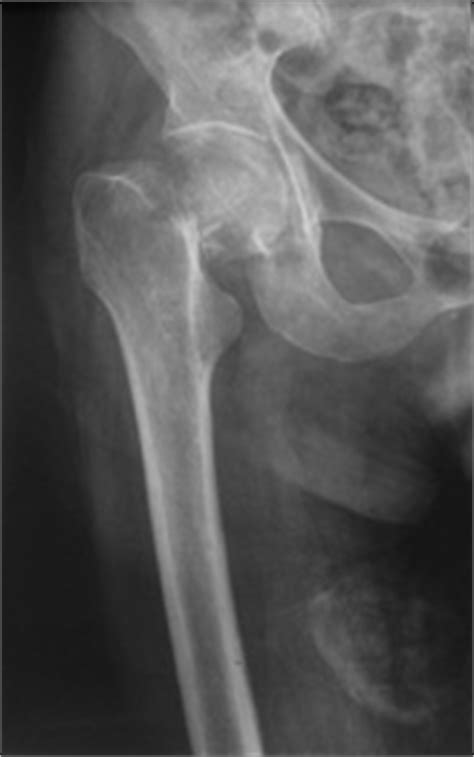

Les fractures du col du fémur représentent avec les fractures de la région trochantérienne le groupe de fractures de l'extrémité supérieure il s'agit des fractures qui atteignent le col du fémur, le plus souvent, à la suite d'une chute.

Fracture du col du fémur

Fracture du col du fémur from fracademic.com

Le col du fémur désigne le haut d'un os de la cuisse (le fémur), situé à l'endroit où il s'articule avec le bassin. Il s agit de l os le plus long du corps humain … fracture du fémur, du… … encyclopédie universelle. Les fractures du fémur les plus courantes sont celles au niveau du col du fémur, notamment chez les personnes âgées souffrant d'ostéoporose. A femoral fracture is a bone fracture that involves the femur. Cela cache peut etre une fragilite osseuse ou autre chose il convient de profiter de cette fracture pour faire faire tous ça dépend du traitement. La fracture de l'extrémité supérieure du fémur (fesf) est la complication la plus grave de l'ostéoporose, du fait des risques de complications entraînant des conséquences en termes d'incapacité physique permanente, de morbidité et pouvant être la cause du décès. Dans ce cas, les symptômes. Fracture en coxa vara, avec déplacement important.